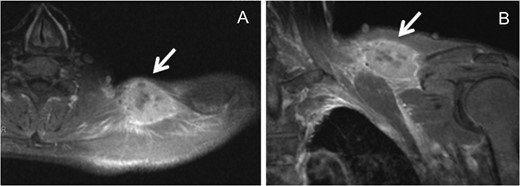

Two years and 3 months after esophagectomy, he complained of pain in the left shoulder. A mass was found between the trapezius and supraspinatus on CT and magnetic resonance imaging (Fig. 3). 18F-fluorodeoxyglucose (FDG) positron emission tomography (PET) demonstrated increased levels of FDG accumulation in the left shoulder. Needle biopsy demonstrated class V (unclear type of carcinoma) disease. Therefore, we performed tumor dissection for muscle metastasis, and the histopathologic diagnosis was SCC. The patient thus underwent adjuvant chemotherapy with S-1 (80 mg/day) administered 4 weeks on/2 weeks off schedule for 1 year.

A hyperintensity mass between the trapezius and supraspinatus on T1-weighted magnetic resonance imaging (A, axial view; B, coronal view).